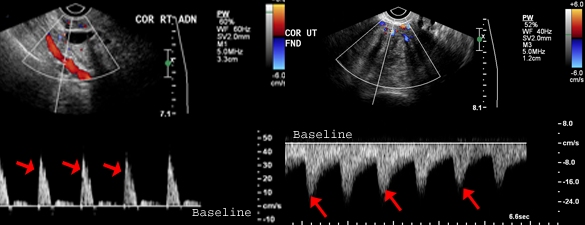

What phase of vascular flow does the red arrow indicate?

Systole

Which of the following describes spectral Doppler flow found surrounding the corpus luteal cyst?

Low-resistance flow